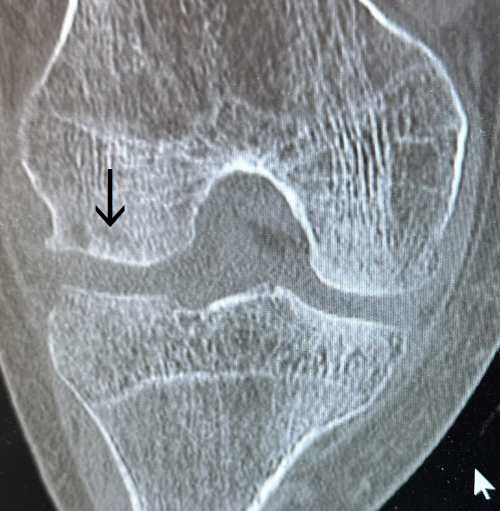

| 特発性膝骨壊死とは、何らかの原因(血行障害など)で膝関節の軟骨下の骨(軟骨は4層からなります。その深層部の石灰化層の下の軟骨下骨)が壊死する疾患です。中高年の女性によく認められます。 大腿骨の内顆に多発しますが、大腿骨外顆、脛骨の内側・大腿骨内顆にも認めます。大半は原因不明です。危険因子として軽微な外傷やステロイド剤の使用歴、アルコールの大量摂取歴、変形性膝関節症に合併して発生することがあります。最近では骨粗鬆症を基盤とした軟骨下脆弱性骨折とも考えられています。 症状 膝の痛みや腫れ、運動障害、歩行障害です。時に、痛みは急激に起こり激痛で、安静時痛や夜間痛を訴えます。変形性膝関節症の症状とは明らかに異なります。 診断 レントゲン検査で4つに分類されます。 ■第一期:異常を認めない。 ■第二期:骨透亮像と骨硬化像が混在する。 ■第三期:軟骨下骨が陥凹し底部に石灰板を認める。 ■第四期:軟骨下骨が修復されず骨壊死となり末期の変形性膝関節症の状態になる。 ただし、第一期はレントゲンでの診断は困難でMRIで診断されます。どの病期にかかわらず詳細な情報を得るにはMRIやCTなどの検査が必要です。 治療 1)保存的治療 保存的治療は早期の症例です。疼痛緩和にアセトアミノフェン、炎症緩和に非ステロイド性抗炎症剤、外皮用薬などを処方します。改善がなければトラマドール塩酸塩、デュロキセチンを検討します。リハビリテーションとして物理療法や運動療法(膝のストレッチング、股のストレッチング、膝の筋力強化、股の筋力強化)を行います。また可動域制限付きサポーターやインソール・装着式足底板(痛みのある側の関節に出来る限り体重が乗らないようにする中敷き)の着用をすすめます。 2)手術的治療 保存的治療で改善されない症例は手術を検討します。壊死の範囲が軽度であれば骨軟骨柱移植術、自家培養軟骨移植術が選択されます。広範囲に破壊された症例は高位脛骨骨切り術や人工関節単顆置換術、人工関節全置換術などが検討されます。